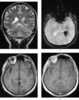

Minimally enhancing intracranial lesion

A traumatic brain injury (TBI), also known as an intracranial injury, is an injury to the brain caused by an external force. TBI can be classified based on severity (ranging from mild traumatic brain injury [mTBI/concussion] to severe traumatic brain injury), mechanism (closed or penetrating head injury), or other features (e.g., occurring in a specific location or over a widespread area). [Source: Wikipedia ]